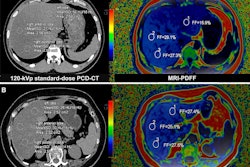

That's where photon-counting CT could prove useful. The technique counts each individual x-ray photon as it passes through the patient, "converting incoming photons into electronic signals proportional to their deposited energy," the researchers wrote -- a quality that appears to translate into reduced radiation dose without affecting image quality. The U.S. Food and Drug Administration (FDA) cleared the first device in September 2021 (Naeotom Alpha, Siemens Healthineers).

Wradzidlo and colleagues compared image quality and radiation dose between a dual-energy CT (DECT) device and a photon-counting CT scanner. Their study included 70 patients who underwent abdominal, contrast-enhanced CT between November 2021 and February 2022. The patients had both a DECT exam and a follow-up exam with a photon-counting device (median time between the two scans was four months). The researchers assessed radiation dose between the two types of studies using the following metrics: CT dose index, dose length product, and size-specific dose estimation. Two radiologists scored the images for quality, particularly lesion visibility.

The group found that photon-counting CT reduced the size-specific dose estimation by 32%, without degrading image quality.

Additionally, the two readers rated lesion conspicuity higher on the photon-counting CT exams compared with the DECT exams, especially in the third quartile, the team noted.

"[Photon-counting CT] enables oncologic abdominal CT with a significantly reduced dose while retaining image quality similar to ... DECT," they concluded.